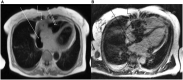

Figure 4

Cardiac magnetic resonance imaging of the patient from March 2020.